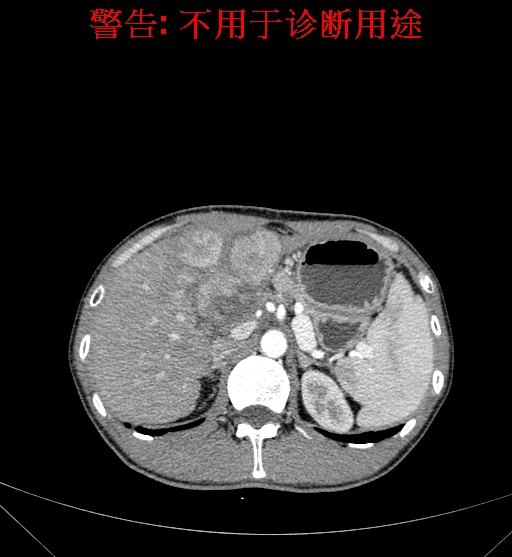

上腹部CT动态增强扫描示肝左叶多发占位性病变,考虑肿瘤,建议MR平扫+增强进一步检查。上腹部MR动态增强示肝左叶肝Ca挤压肝门区结构可能性大,请结合临床综合评价。

术前CT检查:

动脉期